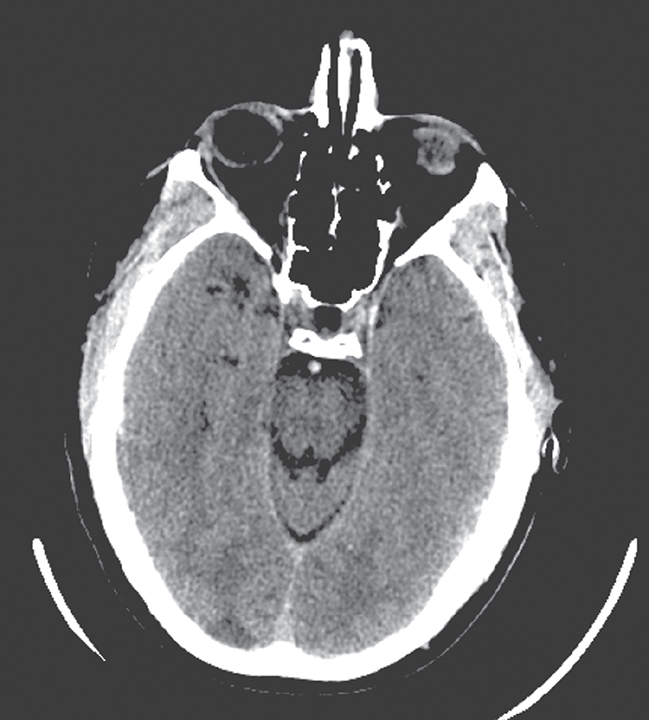

Coma, Cognitive Impairment, and Seizures

- When treating an unresponsive patient, targeted therapy is advised instead of routine use of the “coma cocktail” (empirical treatment with dextrose, naloxone, thiamine, and sometimes flumazenil).

- Avoidance of hypotension and maintenance of normoglycemia and normothermia are critical to the management of intracranial hypertension.

- Differing levels of awareness were noted among patients found to be in a minimally conscious state (MCS); subsequently, this condition was further subdivided into two categories, MCS plus (MCS+) and MCS minus (MCS-), based on the ability to follow commands versus just visual pursuit. Permanent vegetative state is no longer used.